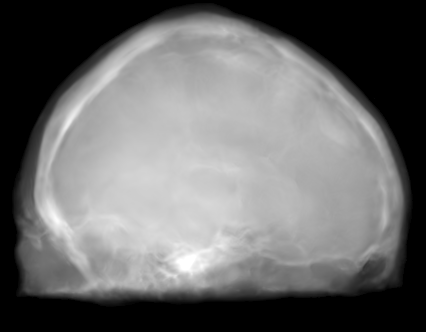

The proposed approach was successful in generating X-ray projections with a contrast similar to the one seen in true fluoroscopic X-ray images. Quantitative results of the generated projection images for all patients are presented in Tab. 2 and for the different network architectures in Tab. 2. In Fig. 2a to 2e the behavior of the MSE and SSIM w.r.t the projection angle is presented. Additional qualitative results of the proposed projection image-to-image translation pipeline for different patient data sets are shown in Fig. 3a to 3c. In Fig. 4 the influence of the modified network architecture, as well as the weighted loss w.r.t. to the edge map are presented.

MRI projection Generated projection Label projection

The improvement in our method compared to the baseline method is demonstrated by a decreased MSE, increased SSIM, and PSNR in Tab. 2. When examining Fig. 4a to 4c, improvements can be observed in the overall increased contrast of high-frequency details. Using the originally proposed architecture [5, 6], which gathers the residual blocks at the lowest resolution level, results in overall blurrier results and missing bone structures as seen in Fig. 4a. In contrast, the projections generated with the edge-weighted loss resemble the label images more closely. This can especially be observed at the base of the head. The projections created without the weighting also produce many high-frequency details in this region, however, these are less specific in comparison with the edge-weighted results. This results in decreased MSE and increased SSIM and PSNR of the projections synthesized using our approach. In addition, unnatural holes in the brain are generated by the baseline architecture. A possible explanation for the fluctuations in the error measure shown in Fig. 2a and 2b is that in our trajectory in the angles around 45 and 135 degrees the projection rays are cast from the side through the brain while around 90 and 180 degrees the angle of incidence is from the front or back side of the skull. In the first case this results in projections that exhibit large homogeneous areas which are easier to synthesize. In the second case, however, the high-frequency edges from the eyes, jawbone, etc. are the dominant structures in the image. A limiting factor of this study is the low number of patient datasets available. However, the amount of variation introduced by forward projecting the volumes is large. Varying projective geometries account for distinctively different structural appearance of the resulting projections. What is of course not covered by these transformations are unique characteristics of individual patients or different pathologies. To investigate the possible translation outcome of these properties larger datasets are required in the future. Also details that are not visible in the MRI projections can not be transferred to the generated images. An example would be interventional devices that are X-ray but not MR sensitive. Regarding subsequent post-processing applications, the question arises how this missing information in the generated projection images should be dealt with, which is subject to future work.